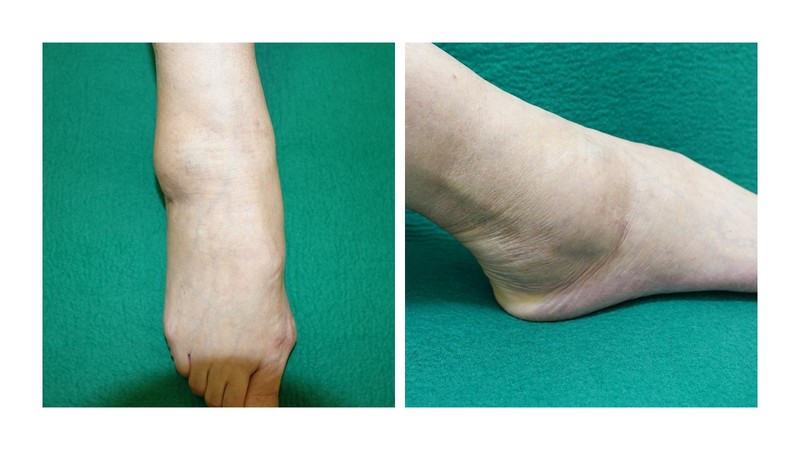

変形性足関節症の主な症状は痛みと腫れです。症状は徐々に進行するため、発病してすぐに重篤な症状が現れることはありません。しかし症状が進行すると、初めは足関節の内側が傷んでくることが多く軽い痛みを感じます。さらに足関節に体重がかかるたびに疼痛(とうつう)を感じたり、足首の可動域が狭くなって坂道を登ることや正座が難しくなったりします。また、外観上は足関節の腫れや内反の変形*がみられます。症状が末期になると、日常生活に支障が出るほどの強い痛みや歩行の不自由さを感じます。まれに歩けなくなるような場合もあります。

内反の変形……足の向きそのものが内側に曲がること